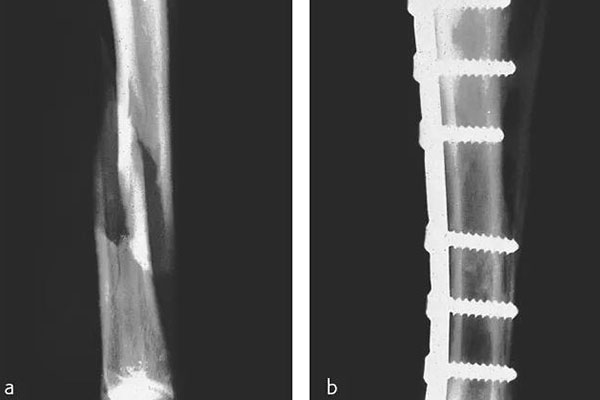

那在检测的时候还需要看到植入物的情况,但由CFPEEK复合材料制成的零件通常具有放射透性,几乎无法通过X射线检测。就通过添加诸如钽丝之类的X射线散射材料,可以使植入物变得可见。可以看下图展示了一个固定骨折骨头的骨愈合板。可以看出,通过设计已对放射密度进行了定制,以便在尽量减少对骨折部位遮挡的同时可视化组件。重要的是,实现X射线可见性的同时也能保持清晰的MRI图像。